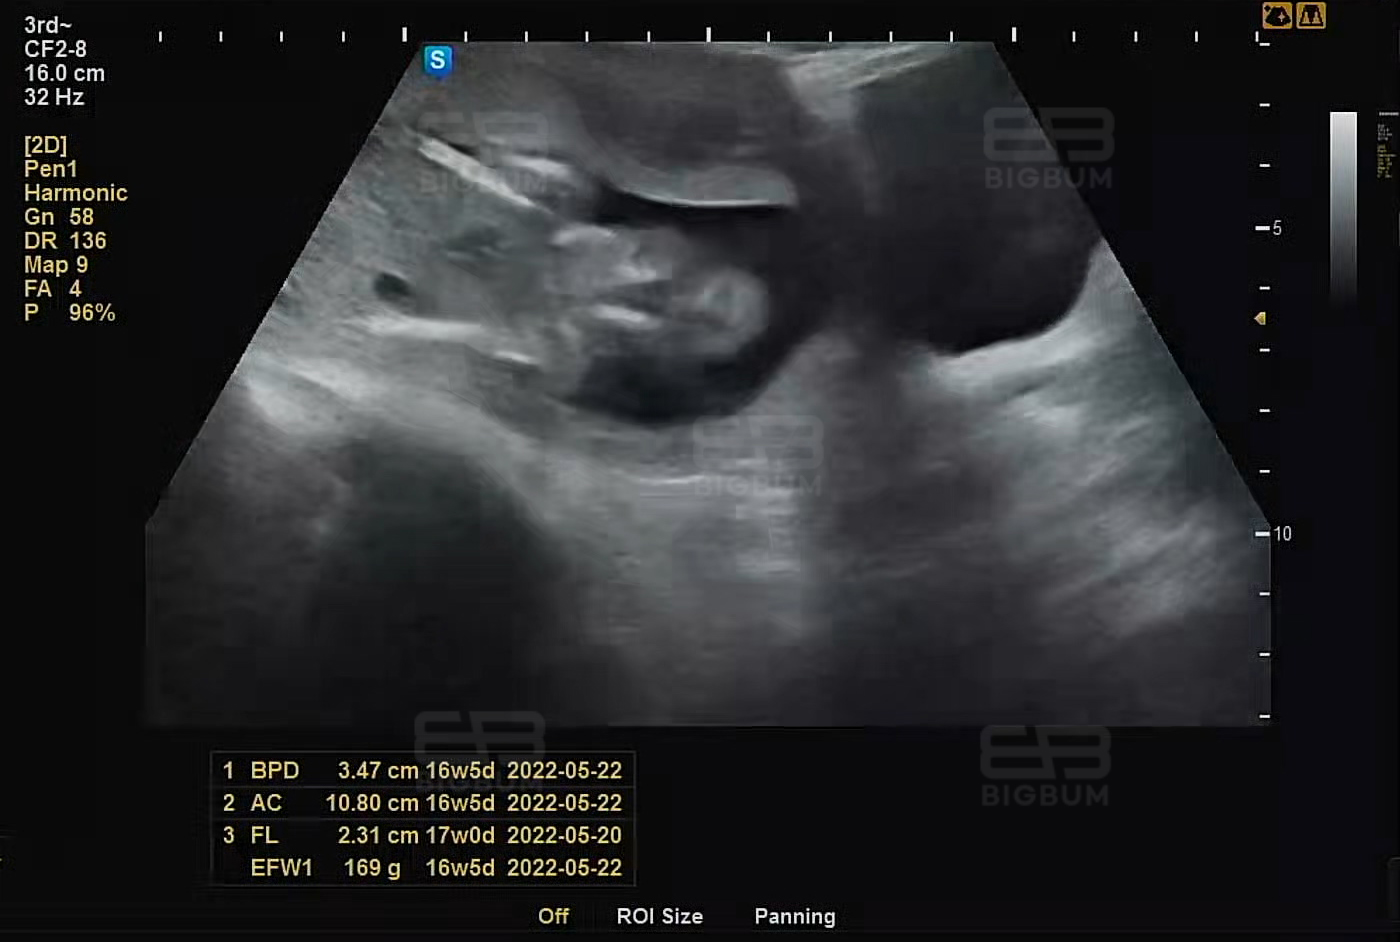

먼저 위 사진 기준으로 +, x 마크는 태아의 전신, 대퇴부, 머리크기 등의 길이 측정을 위한 마크이다. 초음파 검사 시 부위별로 측정 부분 양 끝에 표시를 해 그 사이의 길이를 잰다.

또한 하단에 간단하게 표시된 BPD, AC, FL, EFW1 항목 우측에 16w5d 숫자가 있는데, 이는 측정값에 대한 평균적인 태아의 주수를 표기한 것이다. 16w 5d는 16(week) 5(day)라고 생각하면 된다. 그렇다. 저 초음파 사진은 16주 5일째 되는 날 우리 까꿍이의 복부둘레, 허벅지 다리 길이 등을 측정했을 때 값이다.

주수에 알맞게 성장하고 있는 것이다.